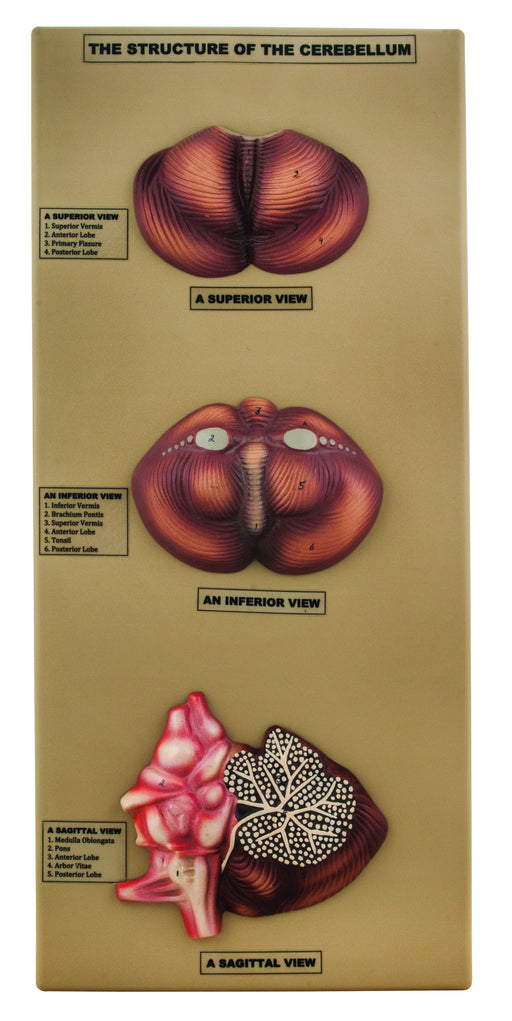

Structure of the Cerebellum

Showing in details a superior view, an inferior view and sagital view of cerebellum. Showing in details a superior view, an inferior view and s...

View full detailsAM0266 -